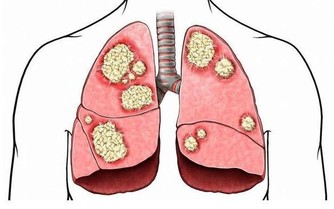

專家說,便秘患者因排便困難,通常會用力過大,引起腹壓升高,血壓也隨之升高;同時心率加快,導致心肌的耗氧量增加,心肌因而發生嚴重而持久的急性缺血,甚至發展為心肌梗死。

便秘患者大便時還常會用力屏氣,擠壓內臟,引起心臟破裂、大血管出現夾層動脈瘤或破裂等,同樣有生命危險。

對心髒病人來說,便秘是引發急性心梗的危險因素之一。患者在用力排便時,血管壓力增加、血流速度加快,容易將附著在血管壁上的斑塊衝進血流,堵塞血管,引發急性心梗,甚至猝死。